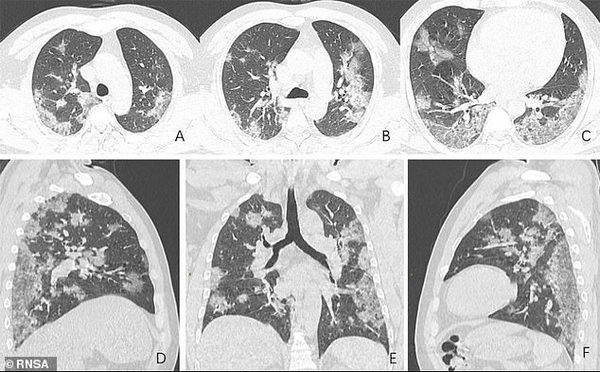

Радиологическое общество Северной Америки показало снимки легких 44-летнего китайца, работавшего на рынке в Ухане.

На кадрах видны увеличивающиеся со временем белые пятна в нижней части дыхательных органов. Также на фото заметно, что присутствие жидкости в легких мужчины постепенно становится все более выраженным.

Китаец был госпитализирован в декабре прошлого года после сильного кашля и высокой температуры. Несмотря на усилия врачей, мужчина через неделю умер.